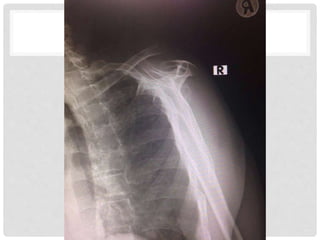

Extremities – Rt shoulder deformity+, tender at AC and CC joint

limit Abduction due to pain

full Adduction, F/E, ER/IR

Radial pulse 2+